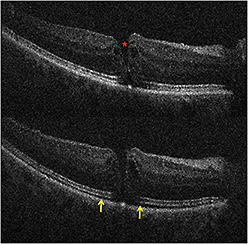

For ERM cases, residual membranes could be identified, and alterations to retinal architecture were also noted (Figure 3, page 28).1,4 Following membrane peeling, changes in the distance between the photoreceptor layers and the retinal pigment epithelium were qualitatively visualized, similar to previous descriptions.1,4,9 These included subtle changes in the hyporeflective band between the photoreceptor layers and the RPE, as well as more significant changes in full-thickness retina.1,9

Figure 3. Intraoperative OCT and ERM. (Top) Preincision intraoperative OCT B-scan revealing prominent epiretinal membrane (orange arrow). (Bottom) Postpeel intraoperative OCT B-scan revealing expansion of the subretinal hyporeflectivity band between the photoreceptor layers and the retinal pigment epithelium (yellow arrows). A residual membrane is also identified (red arrow).

For complex PDR cases, iOCT may provide critical information on surgical planes and identification of residual traction. Rhegmatogenous retinal detachments were also a frequent diagnosis in the PIONEER study (13%). The PIONEER study confirmed previously published findings of frequent persistent subretinal fluid under perfluorocarbon tamponade (Figure 4, page 29).1,5,9

Figure 4. Intraoperative OCT and retinal detachment. Intraoperative OCT B-scan following perfluorocarbon liquid tamponade reveals residual subretinal fluid (yellow arrows).